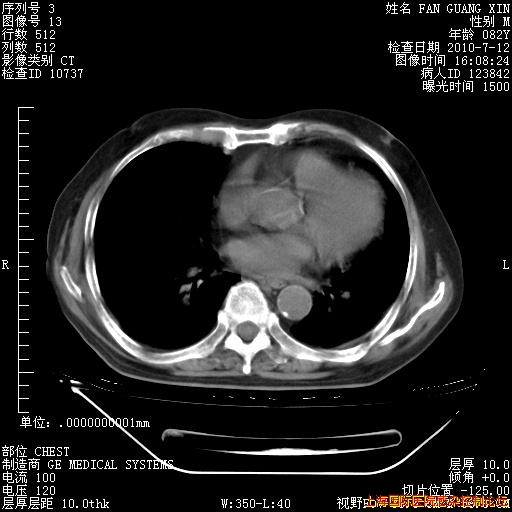

今天复查CT

今天CT

整整相隔30天的肺部CT好像有所好转啊。甲强龙减量第3天,需要观察体温。